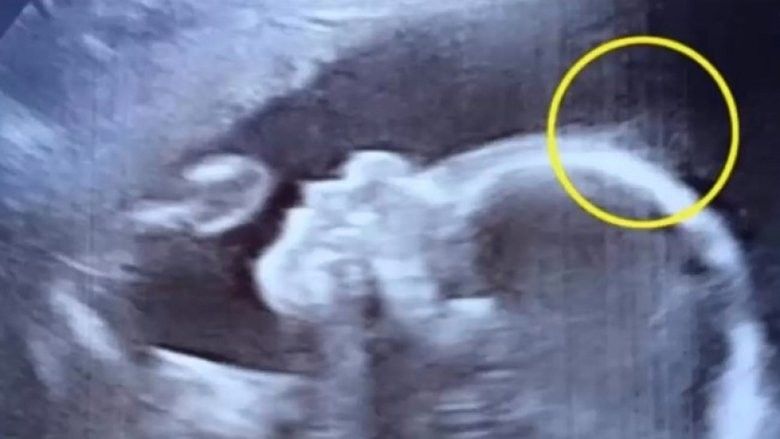

Në kokën e bebes kanë parë linjën e bardhë e cila ndjek formën e kafkës. Doktori për një çast ishte i hutuar, derisa nuk e kuptoi përse ishte fjala.

Kur Natasha Gent ishte në ultrazë, konstatuan që bebja e saj do të lindë me shumë flokë. Mirëpo, kur nëna disa javë më vonë ka dalë në publik me Hollyn e vet të vogël, askush nuk mundi të besonte atë që shihte...

Ashley dhe Natasha kanë pritur bebe me flokë të shpeshtë. Edhe pse këtë e kanë ditur, ishin të befasuar me sasinë e flokëve kur panë vajzën e tyre.